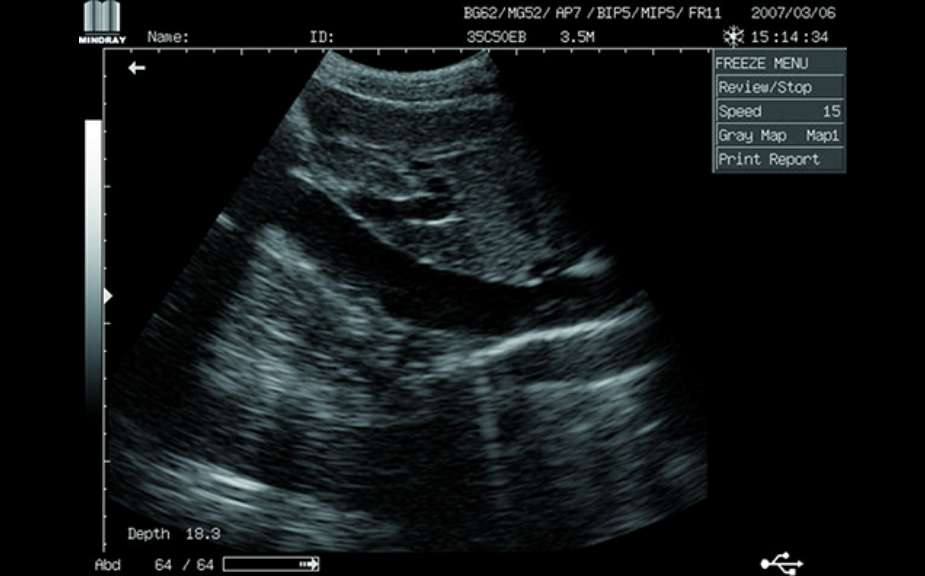

Clinical Images